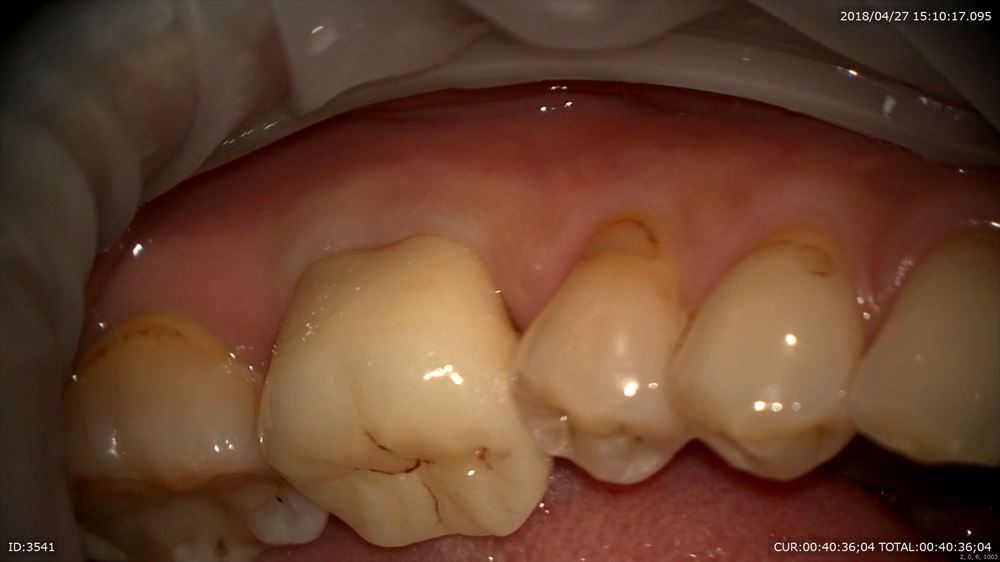

こんにちは。院長の武川です。今日は奥歯にジルコニアのクラウンのセットがありました。

コストパフォーマンスの良い材料で奥歯には私は良く使用します。前歯ですと審美性の観点から(特に透明感が出ない)使用しません。奥歯であれば透明感よりも耐久性の方が優先されます。ですので完璧なフィッティングと強さが優先されたケースの御紹介。

仮歯を外して

歯肉に炎症がない事を確認